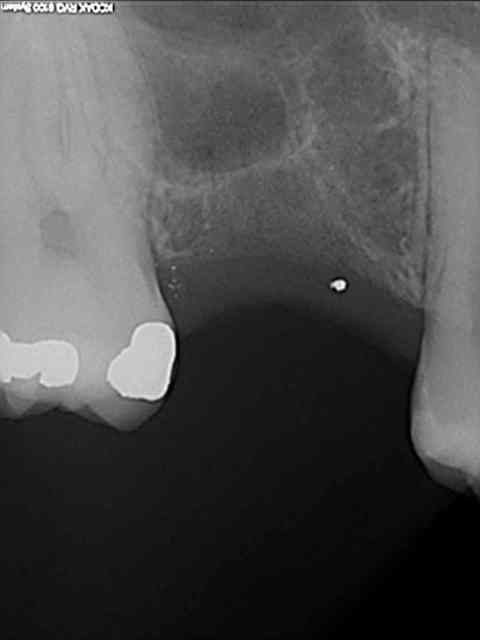

je viens de faire un sinus lift ce matin;

- 3 à 4 mm de hauteur sous sinusienne

- des cloisons de refend partout

- comblement avec du Vital Os

- un implant Axiom D4 L 10

comme je n'avais pas le temps de faire des photos la dernière fois et que j'en étais frustré, je me suis un peu lâcher aujourd'hui...

pour votre plaisir mon ami 8 mois d'écarts

fenêtre fermée par du vitalos pas de membrane technique "grosse ouverture"